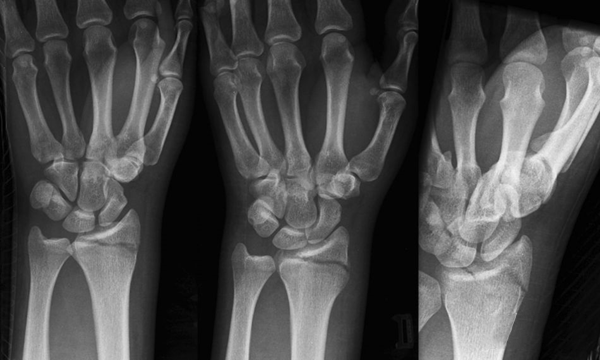

(6)Hutchinson 骨折

又名Chauffeur 骨折、back-fire 骨折、crank 骨折。是桡骨茎突斜行骨折,累及桡腕关节。